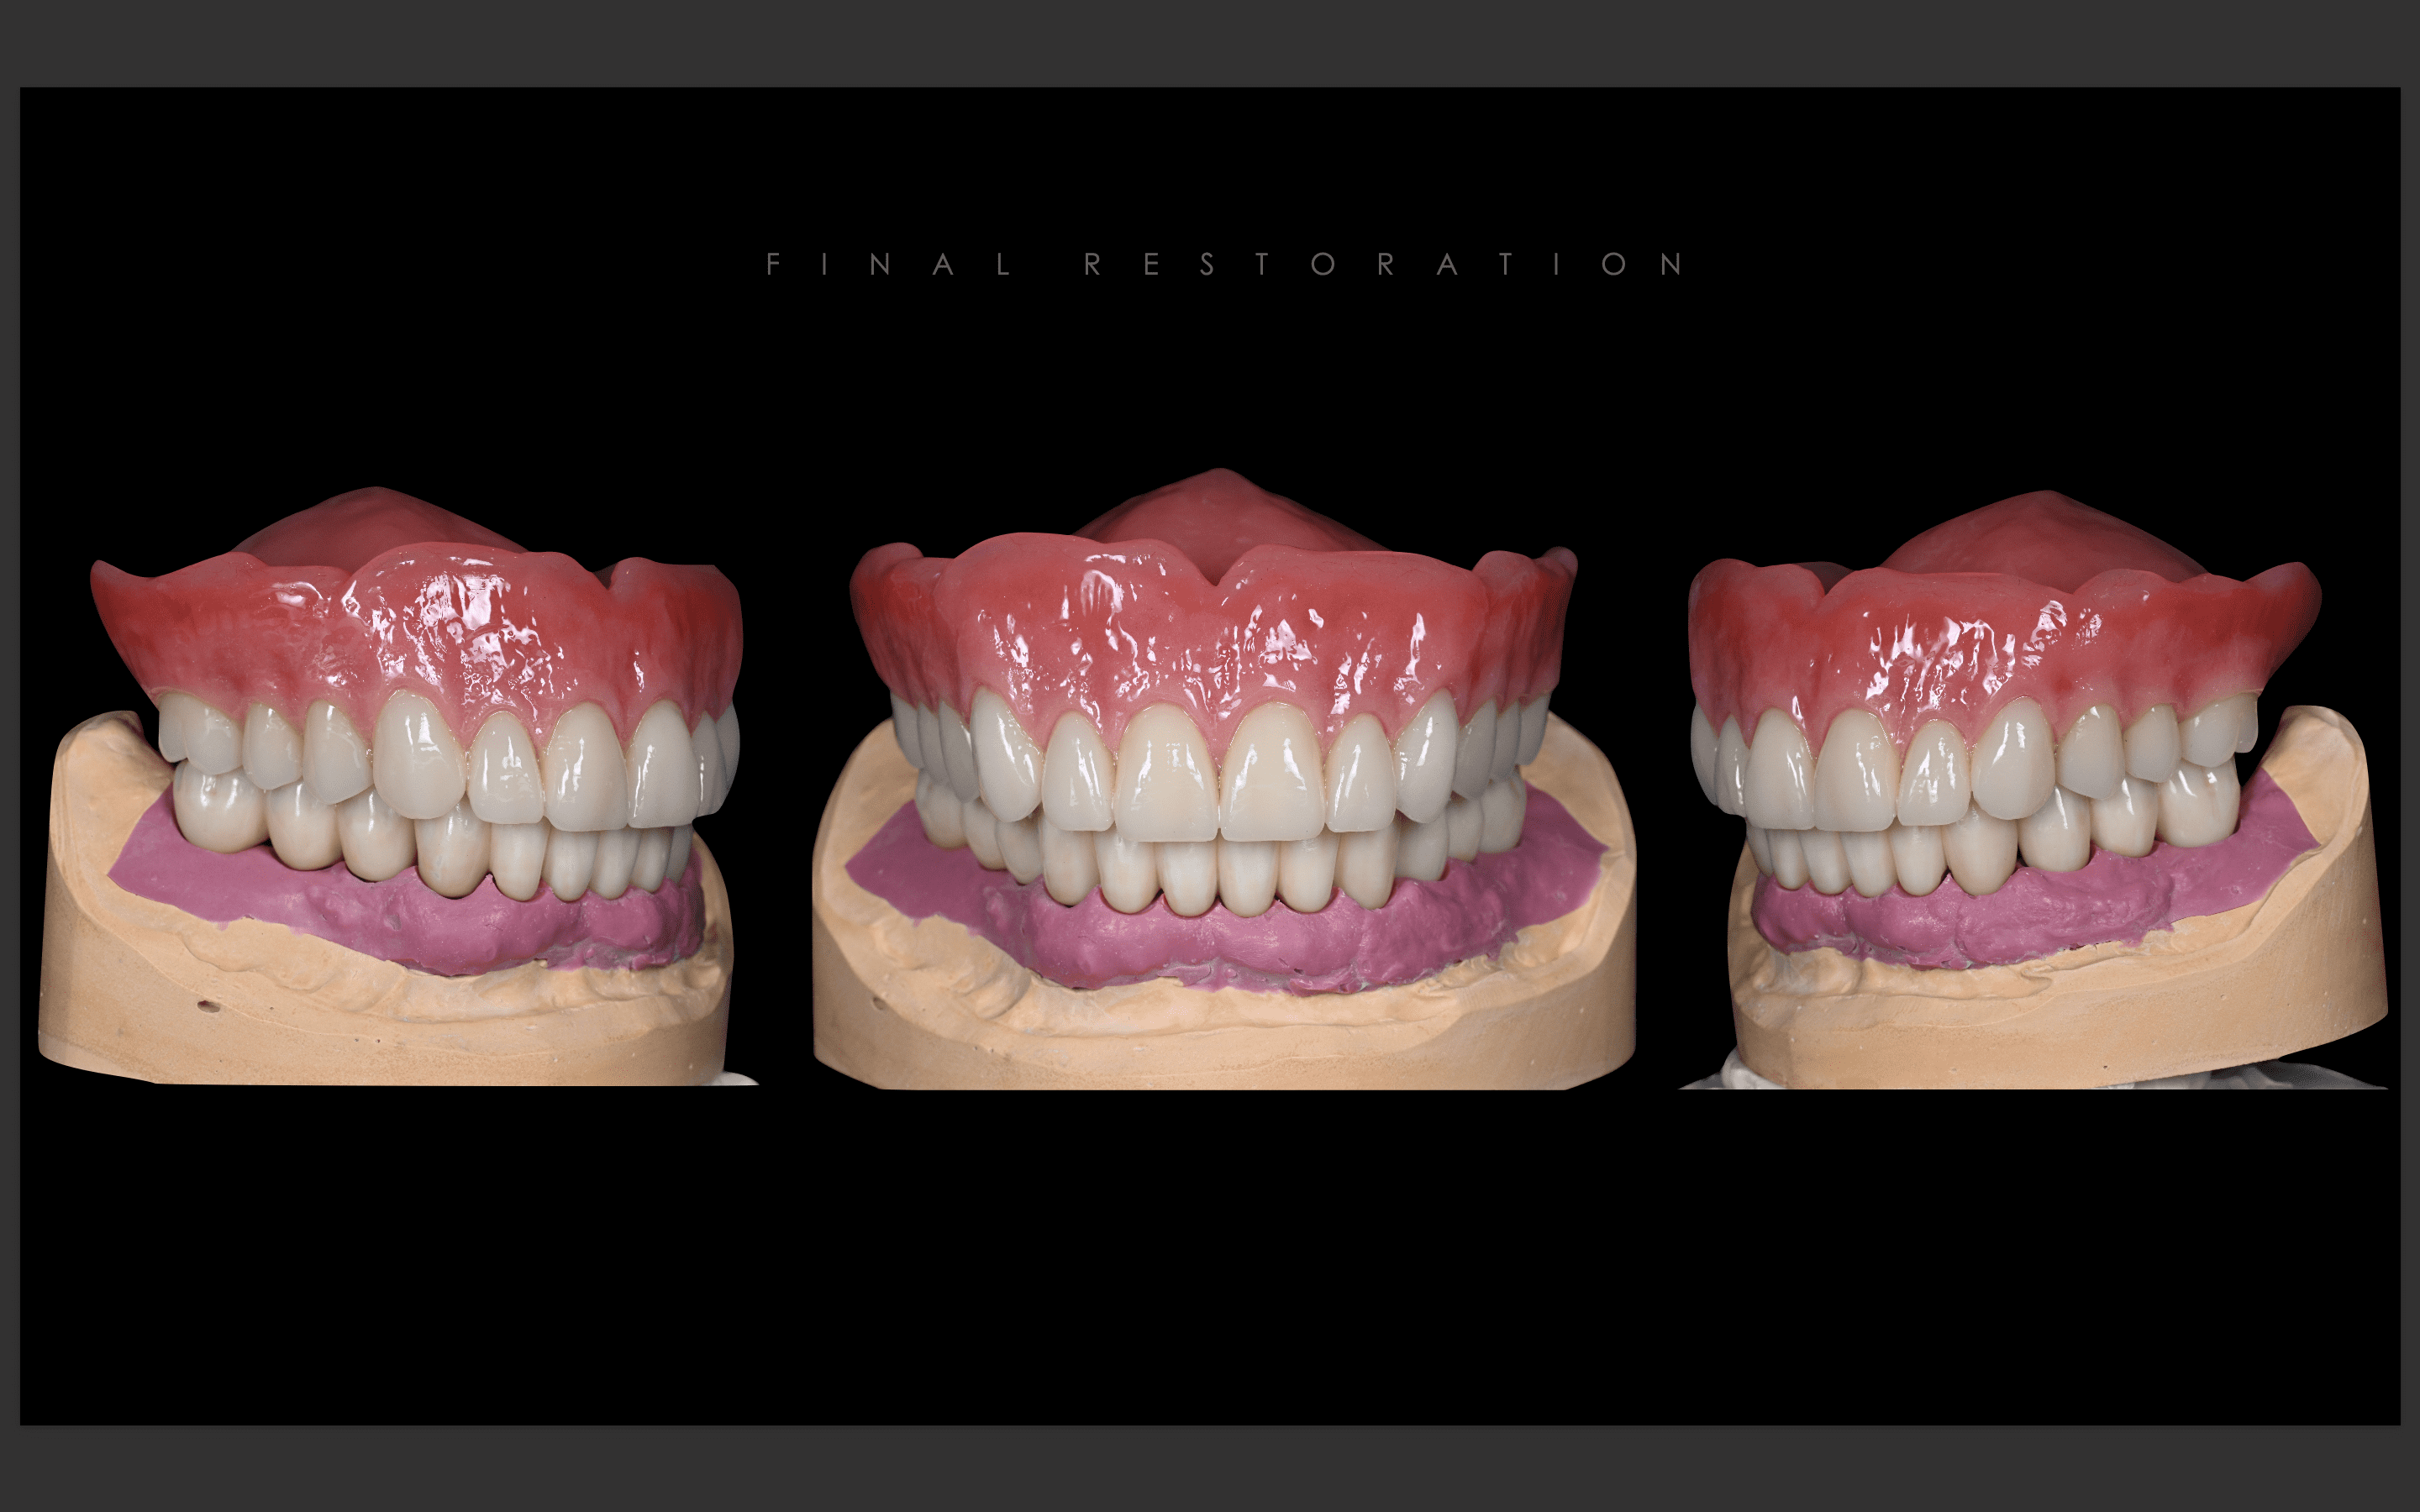

最終補綴

上顎:両側サイナスリフト後のロケーターアバットメントによる金属床ブリッジ

下顎:All-on-6によるフルジルコニアブリッジ